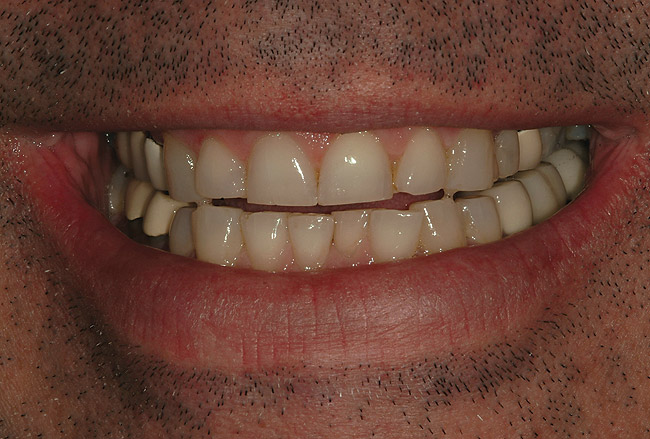

Figure 43  Patient’s postoperative natural smile.

Figure 43